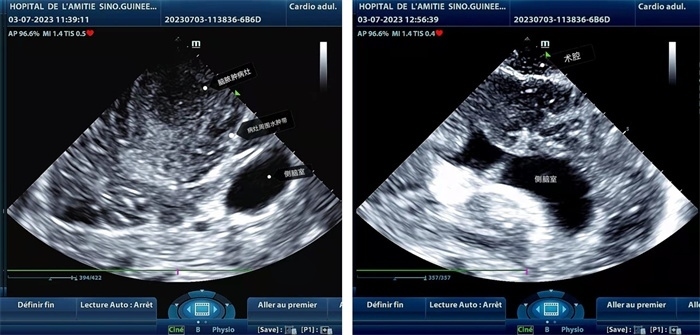

手術(shù)中,張國濱在超聲科顧秀娟的幫助下,運用顱腦術(shù)中超聲技術(shù),通過將一次性保護套的超聲探頭置于腦組織表面,實時觀察病變的位置和形態(tài),進一步確認最佳手術(shù)路徑。術(shù)中超聲顯示,病變位于左額頂葉,大小約為4x4x3cm,邊界清晰,呈囊實性,周邊腦組織水腫明顯。最終,病灶順利切除,診斷為腦膿腫,并通過超聲檢測確認術(shù)腔無病變殘留、無出血,為患者術(shù)后恢復(fù)提供了良好的保障。

左圖顯示術(shù)中超聲見囊實性病變,大小約為4x4x3cm,病灶周圍腦組織水腫明顯;右圖為病灶切除后,術(shù)中超聲示術(shù)腔無病變殘留

左圖顯示術(shù)中超聲見囊實性病變,大小約為4x4x3cm,病灶周圍腦組織水腫明顯;右圖為病灶切除后,術(shù)中超聲示術(shù)腔無病變殘留。中國第二十九批援幾內(nèi)亞醫(yī)療隊供圖